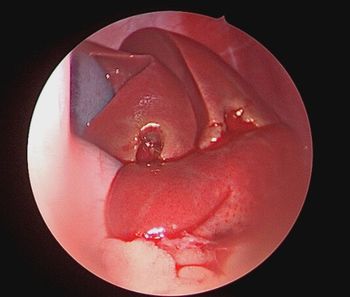

Tibial plateau leveling osteotomy surgery involves changing the anatomy of the knee